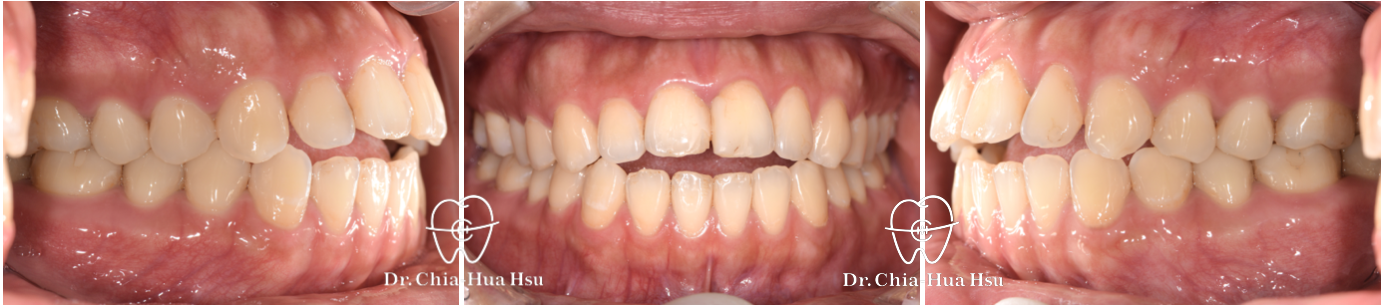

• 病患主訴:從小就前牙開咬,不論是美觀或進食上都困擾許久。

• 問題分析:患者是骨骼一類咬合(Skeletal Class I)合併前牙開咬。

• 治療方式:使用自鎖式金屬矯正器,配合齒間鄰接面修磨,再搭配齒間橡皮筋的使用,使開咬順利解決。另外,也有教導患者正確的舌頭擺放位置與運動練習。

• 治療時間:9個月。

• 治療結果:咬合恢復正常,微笑曲線更自然!